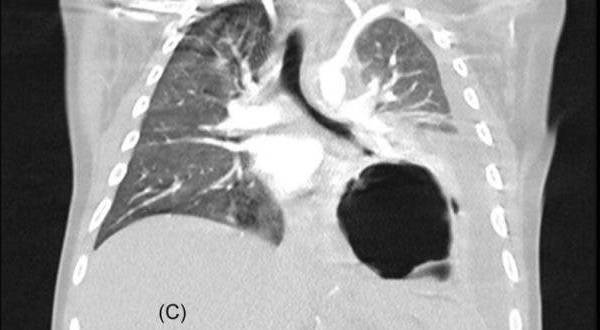

• Inflamación de órganos como corazón, pulmones, riñones, cerebro, piel ojos u órganos gastrointestinales